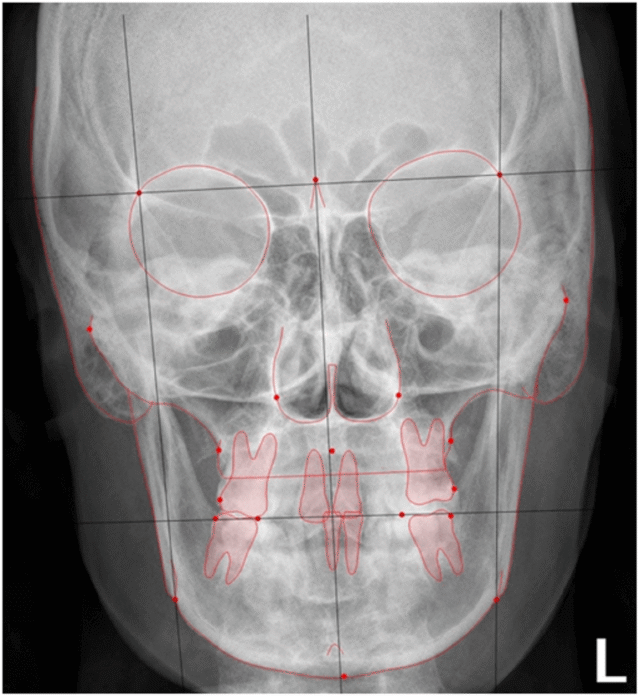

Để chẩn đoán hẹp hàm, bác sĩ chỉnh nha sẽ chỉ định bệnh nhân chụp phim Xquang có tên là Posterior Anterior (gọi tắt là PA) – phim mặt thẳng.

Trên phim PA, bác sĩ chỉnh nha đo đạc các chỉ số, từ đó sẽ khẳng định được nguyên nhân hẹp hàm là do xương hay do răng. Ngoài ra, bác sĩ sẽ phân tích trên mẫu hàm thạch cao khoảng cách giữa 2 răng hàm lớn thứ nhất (răng số 6), nếu khoảng cách này nhỏ hơn 55-60mm (đối vs người VN) thì thường sẽ có chỉ định nong hàm.